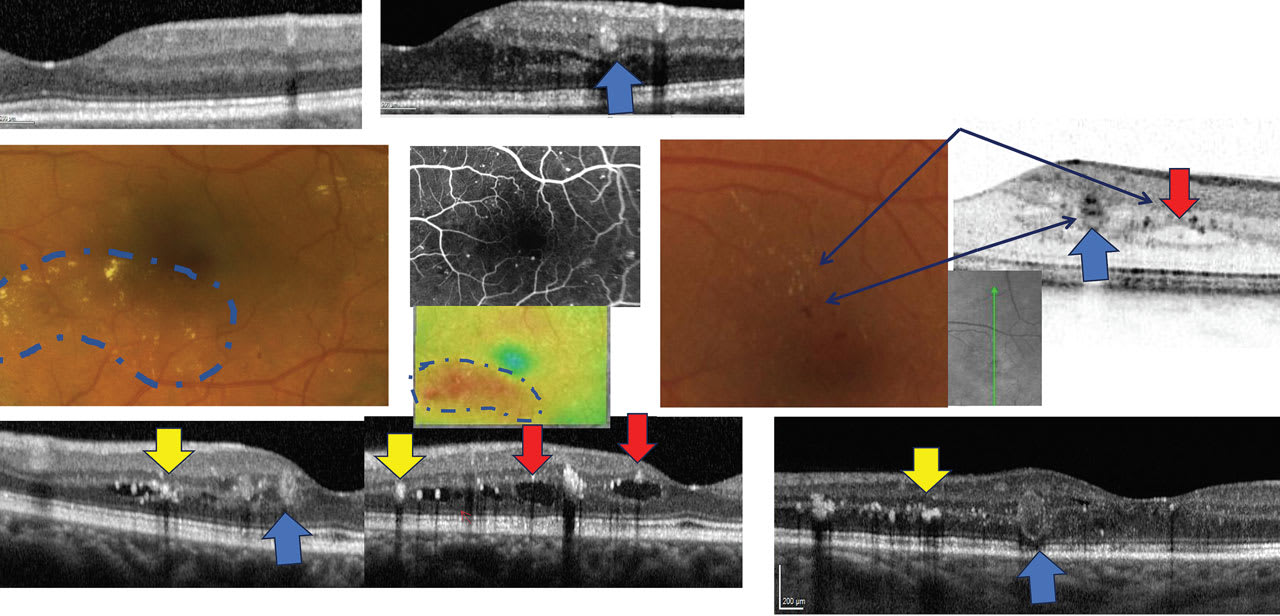

PRACTICE TIP: Use OCT to aid in early identification of diabetic retinopathy

Optical coherence tomography (OCT) can be very helpful in identifying the earliest signs of diabetic retinopathy (DR), write Drs. Roya Attar and Mohammad Rafieetary. Using OCT, optometrists can view microaneurysms (MAs), which appear as small distinct, oval-shaped, hyperreflective, walled structures, and are associated with microvascular damage. To learn more about identifying signs of DR with OCT, read their full article here.